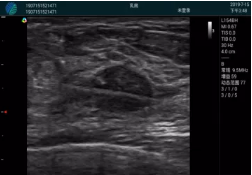

甲狀腺囊性結(jié)節(jié),囊壁鈣化,透聲好

甲狀腺囊性占位